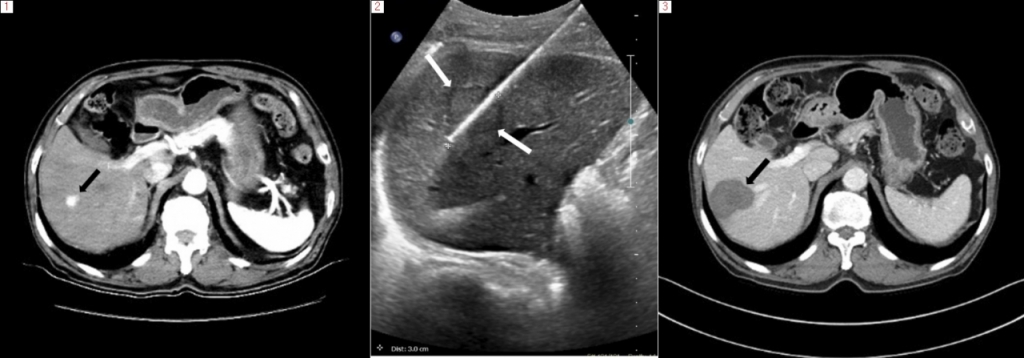

암 치료의 지평이 넓어졌다. CT나 초음파 영상을 보며 전극(냉각)침· 안테나를 종양에 찌른 뒤 에너지를 주입해 암세포를 없애는 '국소 암 절제술'이 수술, 항암, 방사선 치료와 시너지 효과를 내며 암 환자의 새로운 치료 선택지로 부상하고 있다. 국소 암 절제술은 현재 간암, 신장암, 폐암에 국한해 적용 대상이 제한적이긴 하지만 수술에 버금가는 효과를 보이는 것으로 보고된다. 특히 간암(원발성 혹은 대장암으로부터 전이, 3cm 이내, 3개 이내)은 수술과 거의 대등한 치료 성적을 보인다. 신장암 역시 로봇·복강경 수술과 비교해 치료성적은 비슷하면서도 환자 부담이 적어 의료진의 환영을 받는다.

전기 에너지를 열에너지로 바꿔 종양을 없애는 고주파 절제술은 대표적 고열 치료법 중 하나다. 전극침을 CT나 초음파 장비 유도 하에 종양에 위치시킨 후 교류 전류(350kHz-500kHz)를 주면, 극성을 띤 물 분자가 전류의 방향 변화에 따라 빠르게 진동하고 마찰을 통해 열에너지가 생성돼 암세포를 파괴하는 방식이다. 10분간 작동시키면 약 3~4cm의 범위를 치료할 수 있어 종양의 크기가 3cm, 개수가 3개 이내인 경우 적합하다. 그 이상일 때도 전극침을 여러 개 쓰거나 위치를 바꿔 여러 번 적용할 수 있다. 반면 열에너지를 사용하기 때문에 치료 시 통증이 심해 수면 내시경을 할 때보다 강력한 정맥 마취와 환자 모니터링 등 치료 환경이 갖춰져야 한다. 종양 크기가 크거나, 통증을 참기 어려워하는 환자에게는 전신마취를 시행하기도 한다.

극초단파 절제술은 고주파 절제술과 원리와 치료 방식이 비슷하다. 전류를 사용하는 대신 더 높은 주파수(2.4 GHz)의 전자기파를 '안테나'라 불리는 침에 주어 물 분자를 진동시키고 조직을 가열한다. 전자레인지도 극초단파를 발생해 음식을 가열하는 데 이와 동일한 원리다. 고주파보다 더 빠른 시간에 더 높은 열을 생성할 수 있어 상대적으로 짧은 치료 시간에 효과적으로 종양을 제거할 수 있다. 고주파보다 치료범위가 넓고 혈관에 인접한 종양에도 효과적이다. 현재까지 연구에서 고주파 절제술과 비교해 5년 생존율도 비슷한 것으로 보고되고 있다.